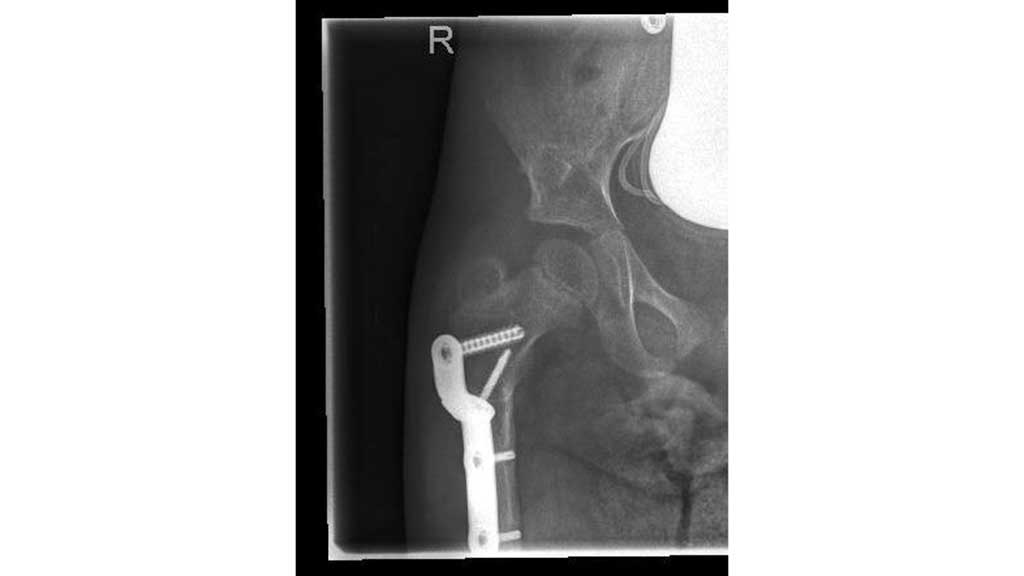

Nach einer ausführlichen Anamnese und der Befunderhebung (ICP, GMFCS V, Frühgeburt 28. SSW) sowie der Röntgendiagnostik steht fest, dass die rechte Hüfte subluxiert ist (Abb. 7).

Im Frühjahr 2012 erfolgte dann die umfangreiche Hüftoperation: Adduktorentenotomie beidseits, Psoas-Tenotomie rechts, offene Reposition und DVO und Pfannendachplastik nach Dega mit Surfixplatte rechts (Abb. 8).